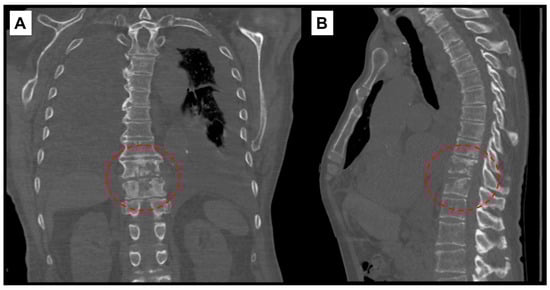

The following day, additional studies revealed elevated pro B-type natriuretic peptide (2337 pg/mL; ref. range: <300 pg/mL), sedimentation rate (39 mm/hr; ref. range: 0–20 mm/hr), and high sensitivity C-reactive protein (hsCRP) (69 mg/L; ref. range: 0.1–3 mg/L). A CT scan of the chest without contrast demonstrated findings compatible with discitis and osteomyelitis at T10–T11 level (Figure 1), moderate to large bilateral pleural effusions with associated compressive atelectasis of the adjacent lower lobes, consolidation of the right middle lobe, cardiomegaly, a small pericardial effusion, lung nodules measuring up to 1 cm, scattered calcified granulomas, and mildly enlarged intrathoracic lymph nodes.

Figure 1. Computed-tomography scan of chest showing T10–T11 discitis and osteomyelitis. (A) Coronal view with red, interrupted circle highlighting destructive changes to vertebral bodies. (B) Sagittal view.